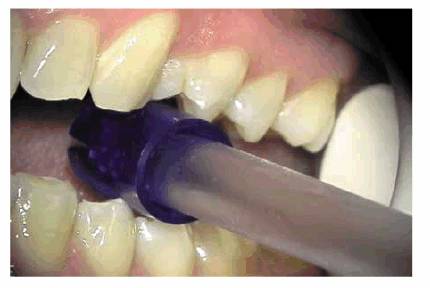

in sterilized anesthetic cartridge and removed) (Figure 19-11) or an ice cube was the only

Figure 19-11: An ice pencil being applied to a maxillary central incisor tooth.